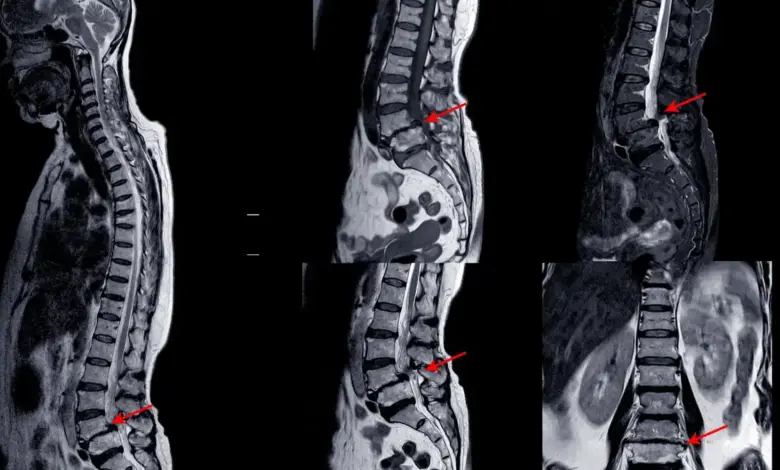

- Ressonância magnética esclarece disco, raízes e medula.

O achado de espondilodiscoartrose cervical em C5 C6 deve sempre ser correlacionado com os sintomas.